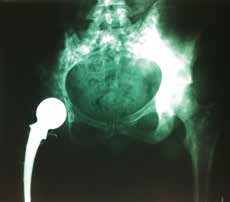

Im Alter von 14 Jahren wurde bei der Patientin ein Osteosarkom im rechten distalen Femur diagnostiziert. Der Tumor befand sich an der Medial- und Dorsalseite des Femurs bis handbreit oberhalb des Kniegelenkspaltes. In weiteren Untersuchungen wurden Markraumveränderungen bis knapp unterhalb des Trochanter minor festgestellt. Aufgrund dieses Ausmaßes erfolgte eine Hüftexartikulation mit direkter Implantation einer Großkopf-Endoprothese. Um die Versorgung mit einer Hüftex-Prothese zu umgehen, wurde in der Operation das natürliche Acetabulum erhalten, die Großkopf-Endoprothese implantiert und somit die Möglichkeit gegeben, die Patientin mit einer OS-Prothese zu versorgen. Der Schaft der Endoprothese wurde mit Knochenzement ummantelt, um die Rekonstruktion der Muskelansätze zu ermöglichen (Abb. 1a u. b). Aufgrund der durch Myodese rekonstruierten Muskulaturansätze ist die Weichteildeckung vor allem im distalen Bereich als eher ungünstig zu bewerten; das distale Ende des mit Knochenzement ummantelten Endoprothesenschaftes ist deutlich zu ertasten (Abb. 2).